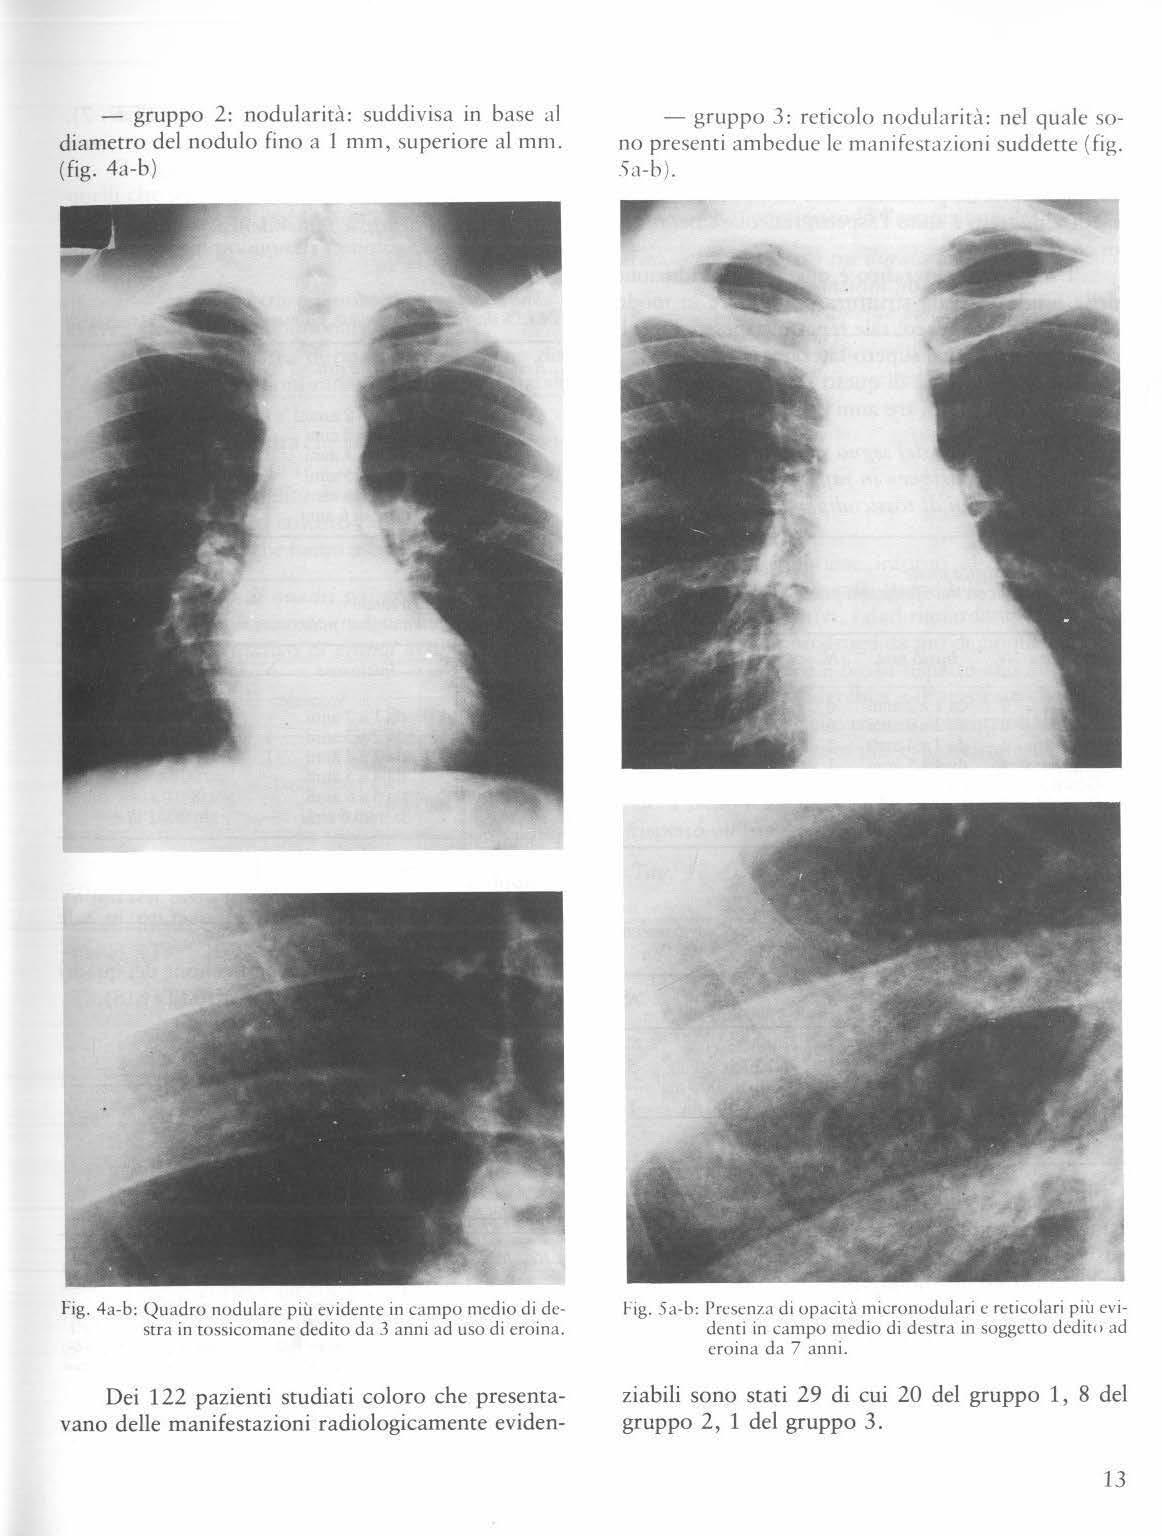

- gruppo 2: nodularità: suddivisa in base al diametro del nodulo fino a I mm, superio re a l mm. (fig. 4a-b )

- gruppo 3: reticolo nodularità: nel quale 'iOno presenti ambedue le manifestazioni suddette (fig. .'ia-h )

Fig. 4a-b: Quadro nodulare più evidente in campo medio di destr a in tossicomane dedito da 3 ann i ad uso di ero in a.

l'ig. 5,1-b: Presenza di opaci t à micronodulari e reticolari più evidenti in camp o medio di destra in soggetto dedit,, ad eroina da 7 anni.

ziabili sono stati 29 di cui 20 del gruppo 1 , 8 del gruppo 2, 1 del gruppo 3.